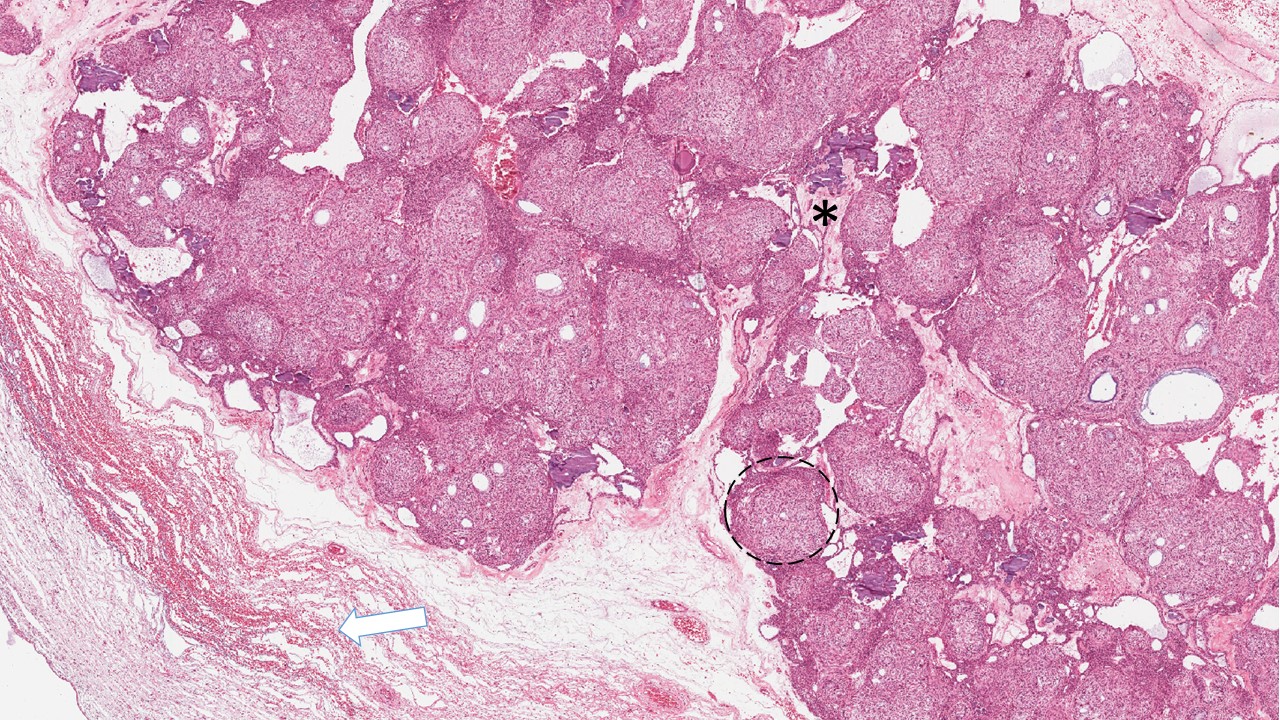

Descrição microscópica:

Nota-se grande deposição de tecidos dentários, na maior parte, de dentina com características de dentina tubular madura. Em áreas observa-se fendas ou espaços claros (esmalte maduro que foi removido durante o processo de descalcificação). No interior destes espaços podem ser observadas quantidades pequenas de matriz orgânica de esmalte ou esmalte imaturo. Revestindo essas áreas nota-se células epiteliais odontogências interpretadas como ameloblastos e focos de células epiteliais frouxamente arranjadas lembrando o reticulo estrelado do órgão do esmalte. Tecido conjuntivo lembrando a polpa dentária podem ser identificados mostrando camada de odontoblastos na periferia. Uma delgada camada de cemento com frequência está presente na periferia da lesão.

Dados importantes para diagnóstico:

- Abundância de tecido dentinário (asteriscos pretos);

- Matriz orgânica de esmalte (asteriscos brancos);

- Ameloblastos (setas brancas);

- Células semelhantes à do retículo estrelado (setas pretas);

- Tecido conjuntivo lembrando a polpa dentária com camada odontoblástica (triangulo);

- Espaço do esmalte dentário (perdido na descalcificação)